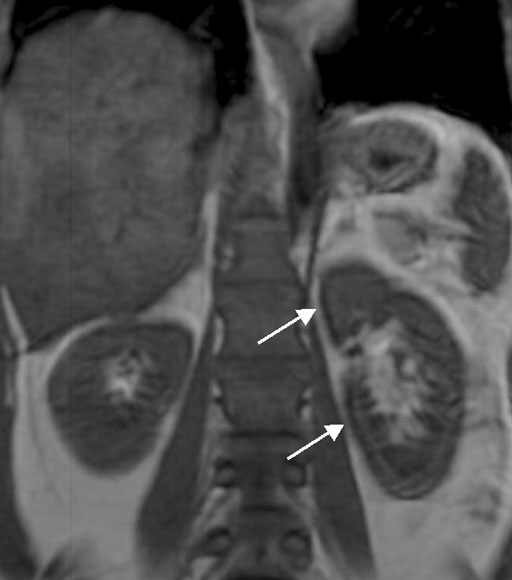

T1,T2強調画像ともにhemogiderin沈着を反映し、腎皮質が低信号を呈している(白矢印)